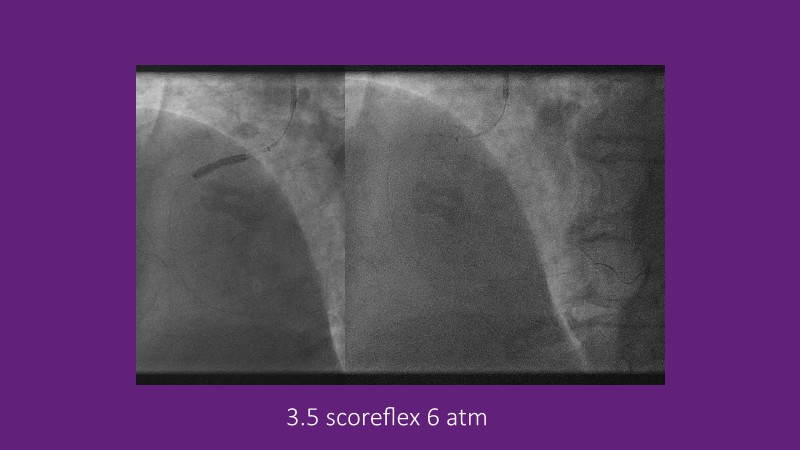

Explore cutting-edge strategies for optimizing drug-coated balloon (DCB) procedures in this session. Uncover practical tips to improve outcomes, review key indications, and examine international consensus on DCB use. Case presentations and expert discussions offer insights to refine your approach.

- To learn the tips and tricks to improve the result with drug coated balloon strategy